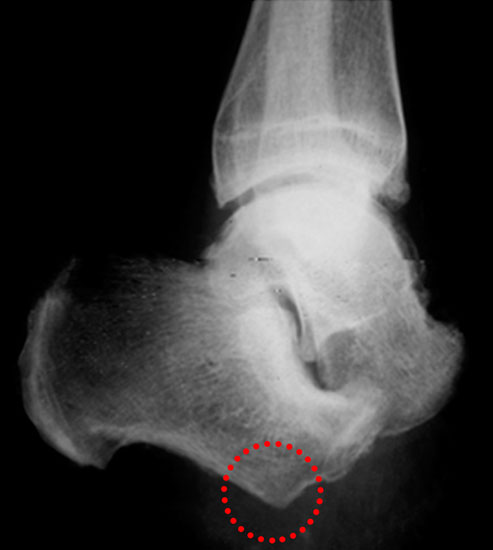

Der kraniale Calcaneus wird so mit der oszillierenden Säge reseziert, dass bei der Fusion mit der Tibia die physiologische Inklination von 30° wieder hergestellt wird (Abb. 48). Wird der Calcaneus zu steil eingestellt, kann das zu erhöhter Druckbelastung am Tuber calcanei und damit zur Ulzeration führen. Eine flache Einstellung des Talus wird von manchen Operateu­ren bevorzugt. Dies ist technisch vielleicht etwas einfacher, führt jedoch zu einer stärkeren Verkürzung. Varus- und Valgusfehlstellungen müssen vermieden werden.

Zur Osteosynthese bevorzugen wir 2-3 kanülierte Großfragmentschrauben (Abb. 49). Postoperativ ist die Extremität für 8 Wochen zu entlasten, wobei zur Sicherheit eine Entlas­tungsorthese verordnet werden kann. Bei schwachen oder unzuverlässigen Patienten empfiehlt es sich, für 8 Wochen einen Ring-Fixateur anzulegen.